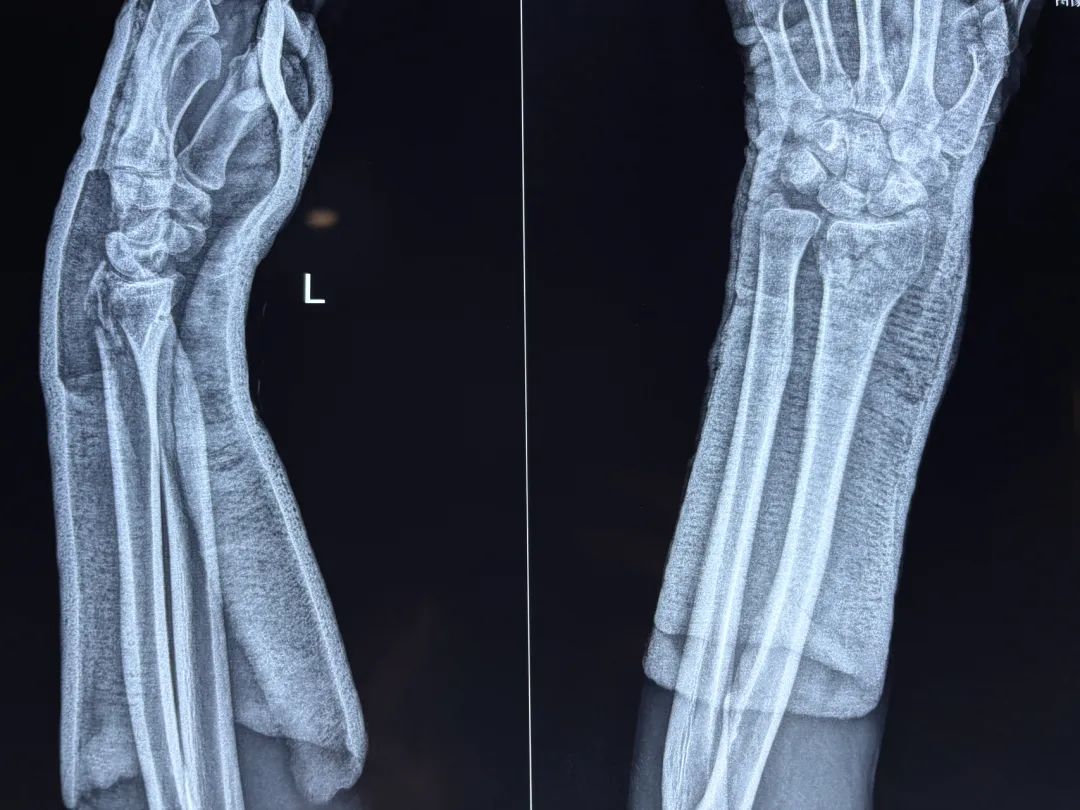

对绝大多数新鲜桡骨远端骨折,国内外均采用手法复位、外固定(石膏、夹板、功能支架等)方法进行治疗 手术疗法只适用于极少数严重挤压并短缩畸形。

复位手法:

牵抖复位法:术者两手紧握手掌,两拇指并列放于远折段背侧,其它四指量于腕掌部,扣紧大小鱼际部,顺原移 位 方 向 持续牵引,助手握住上臂近肘部,作反牵引,术者一边牵引,一边轻轻上下摇摆,听到骨擦音时 即说明嵌插已分开。

⼀ 般 ⻣ 折远 端 稍 旋 前 , 牵 引 过 程 中 可 稍 旋 后 , ⽽ 后 持 续 牵 引 下 , 顺 纵 轴 ⽅ 向 骤 然 猛 抖 , 同 时 迅 速 尺 偏 掌屈 , ⻣ 折 即 可 复 位 , 但 切 忌 旋 转 ( 尺 偏 时 易 旋 前 ) 。